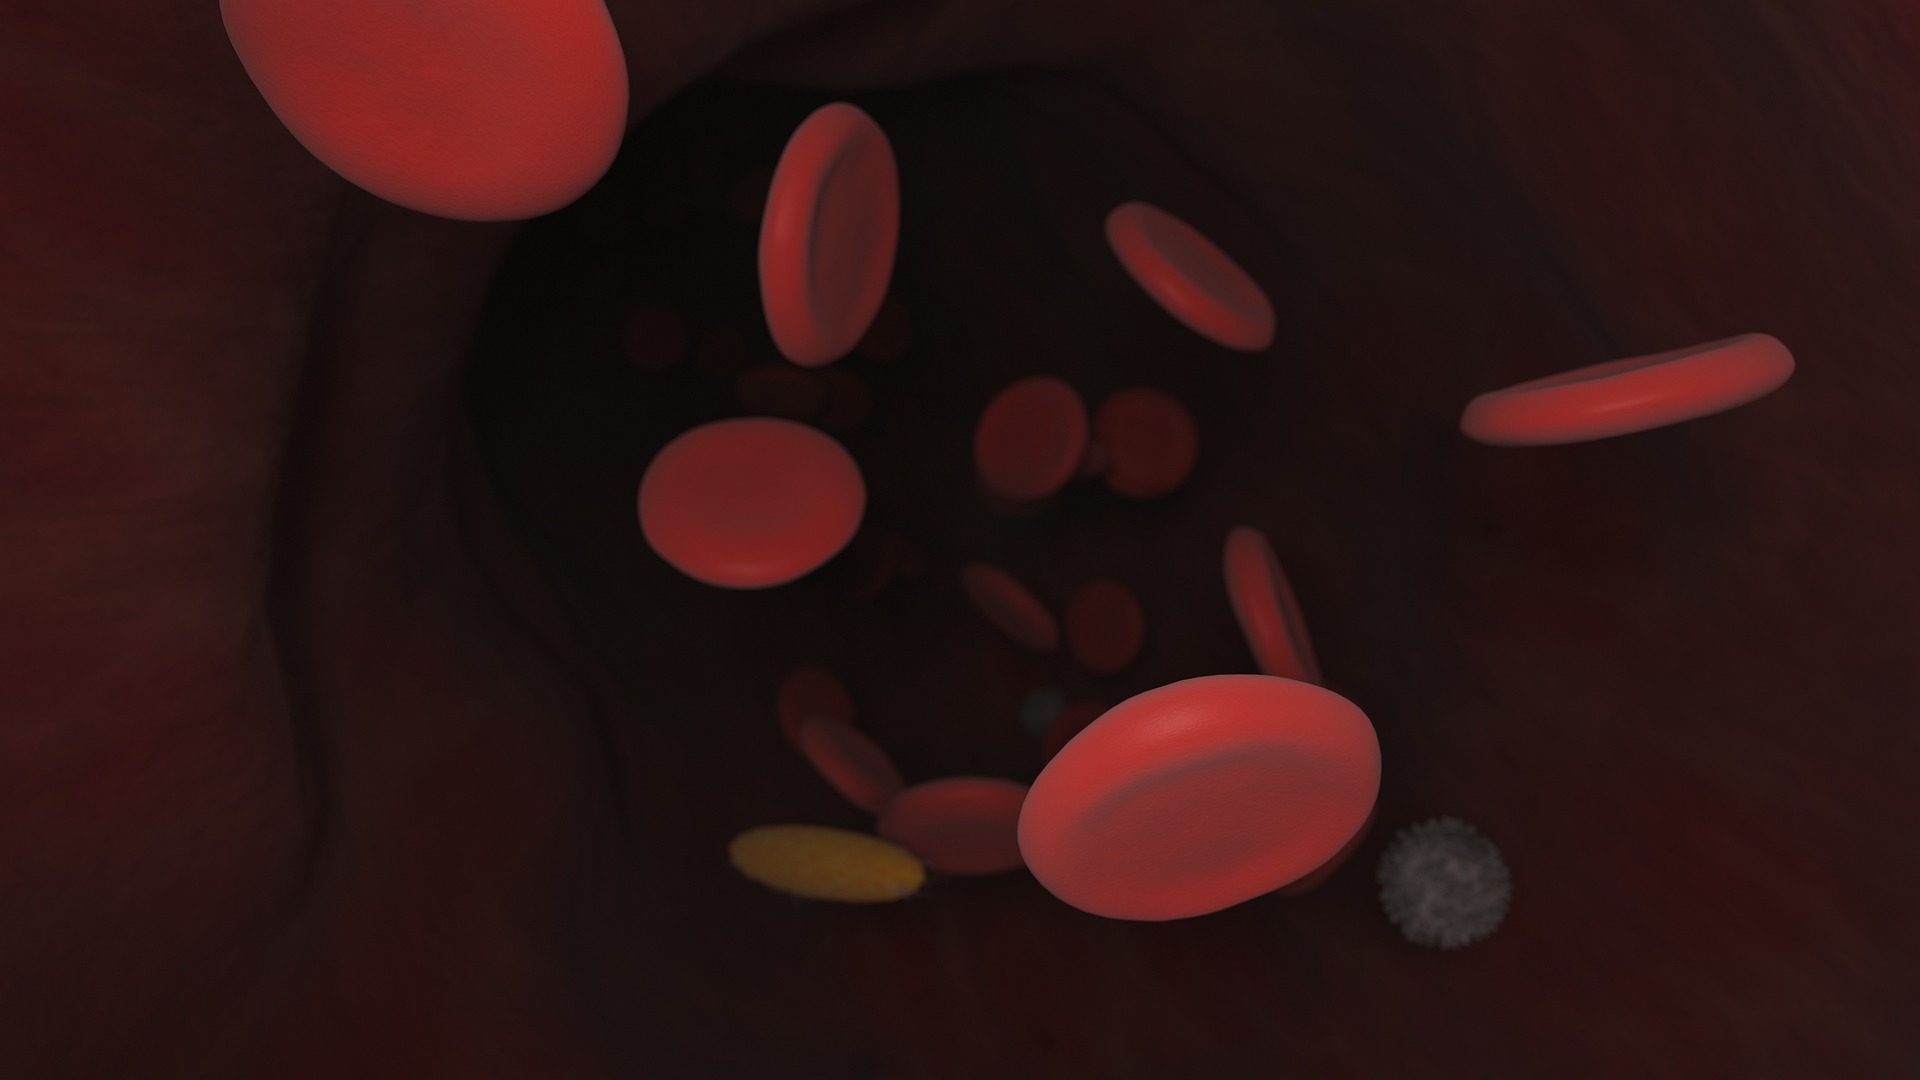

Jakarta (Indonesia Window) – Para ilmuwan dari Universitas Far Eastern Federal bersama dengan rekan mereka dari Rusia dan Jepang berpendapat bahwa virus corona dapat menyerang sumsum tulang merah, yang tidak hanya merusak sel darah merah tapi juga mencegah pembentukan sel baru.

“Para peneliti berpikir bahwa kelompok berrisiko termasuk orang-orang dengan jumlah hemoglobin rendah karena eritrosit, sel darah merah yang bertanggung jawab untuk transfer protein hemoglobin yang jenuh besi, adalah target utama virus. Kesimpulan ini dibuat oleh kelompok penelitian internasional yang mempelajari mekanisme perkembangan infeksi virus corona (COVID-19),” kata pernyataan itu.

Para ilmuwan berpikir bahwa kelompok berrisiko mencakup semua orang dengan jumlah hemoglobin rendah.

Mereka adalah para lansia, penderita tekanan darah tinggi, obesitas, diabetes, ibu hamil, penderita imunodefisiensi, penderita kanker, dan sebagainya.

Menurut Galina Reva, profesor di Departemen Kedokteran Fundamental dari School of Biomedicine dari Far Eastern Federal University, virus berkembang biak di kulit dan kemudian masuk ke darah dan menyerang target yang mungkin termasuk kedua sistem internal (saluran pencernaan, paru-paru, sistem genitourinari) dan sel darah merah.

“Kami berasumsi bahwa tujuan utama virus adalah sumsum darah merah, di mana ia merusak endotelium yang biasanya mengatur migrasi sel yang sedang tumbuh ke darah,” jelasnya.

“Itulah mengapa hal-hal aneh terjadi dengan sel kekebalan, dan di jaringan berbagai organ megakariosit, ditemukan sel-sel sumsum tulang yang sangat besar,” imbuh Reva.

“Biasanya, megakariosit adalah sumber trombosit yang bertanggung jawab dalam kemampuan pembekuan darah, tapi dengan COVID-19 mereka mengentalkan darah di pembuluh darah yang tidak perlu,” katanya.